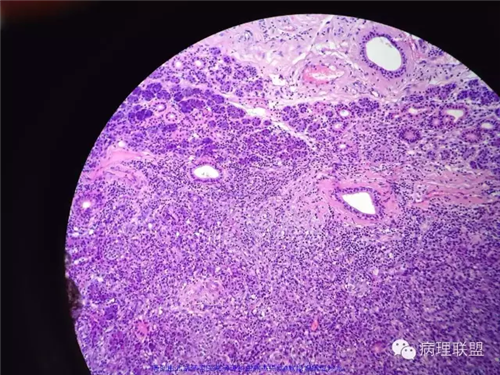

甲状腺肿物,镜下梭形细胞肿瘤,伴坏死及钙化,侵犯横纹肌及涎腺,不知道各位老师考虑什么,免疫组化还没有方向,低分化恶性梭形细胞肿瘤?炎性肌纤维母细胞肿瘤?甲状腺原发还是涎腺原发?谢谢。

首先除外癌,如间变性/肉瘤样癌,其次考虑软组织来源。

我考虑UTC,年龄+体征+组织学图像,考虑UTC,发展很快。

好吧 俺也瞎叨叨几句:1,这一例的关键是确定和甲状腺的关系。虽然大体以及描述都说的是甲状腺,但图中没示任何甲状腺。如果找到正常甲状腺组织,当然可以;如果找到其他甲状腺高分化癌的成分,也有提示意义,2,临床表现,80岁,先倾向于UTC了;如果生长再迅速一点,那更支持了。3.镜下,UTC的几个特点(i) widely invasive growth, (ii) extensive tumor necrosis, (iii) marked nuclear pleomorphism, and (iv) high mitotic activity. 此处的坏死,是geographic coagulative necrosis,所以俺才说是有特点。